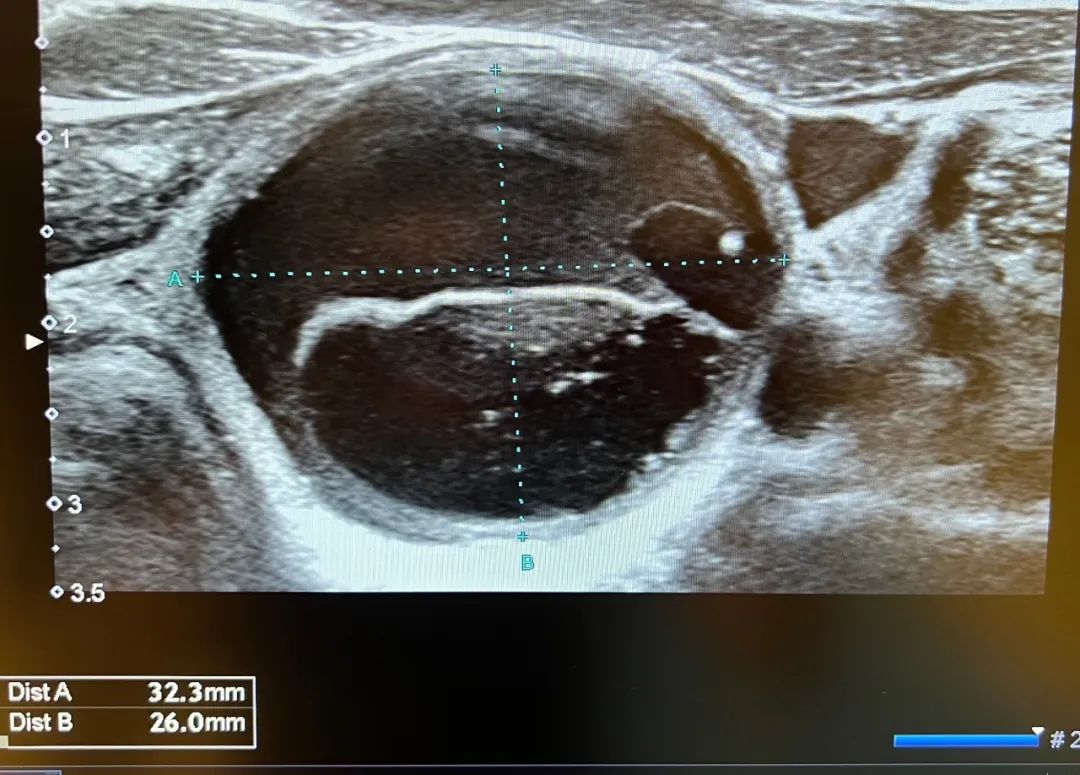

内容提要 2025年7月4日,葫芦岛市第二人民医院超声科王云霞主任团队完成辽西首例超声引导下甲状腺囊肿聚桂醇硬化治疗术,53岁的赵女士(化名)成为首位受益者——仅通过一个1毫米针眼,便解除了困扰多年的3.2厘米囊肿。这项以“精准、微创、高效”为核心的技术,标志着辽西甲状腺疾病微创治疗进入新阶段! PART.01 病例回顾 囊肿增大压迫生活,微创治疗成首选 赵女士数年前体检发现甲状腺结节,近期复查其甲状腺右叶囊肿已增大至3.2×2.6cm,导致颈部肿胀、呼吸吞咽异物感等压迫症状,严重影响生活质量。传统开放手术虽能切除囊肿,但存在创伤大、恢复慢及颈部留疤等问题,而王云霞团队采用全新引进的国际领先超声引导下聚桂醇硬化治疗术,仅使用1毫米细针,术后不留疤痕,赵女士欣然接受了手术方案。 术前照片及影像 PART.02 填补空白 毫米级“针功夫”化解囊肿危机 术中视频 手术在局麻下进行,超声科王云霞、邓兆姝主任团队通过一根直径仅1mm的细针,精准避开甲状腺血管和神经,穿刺至囊肿内部,抽尽囊内液体,缓解囊肿对周围组织的压迫;注入聚桂醇硬化剂反复冲洗囊壁,破坏内皮细胞,诱发无菌性炎症反应;保留部分聚桂醇溶液。整个过程仅耗时30分钟。术后赵女士颈部只留一个针眼,无任何并发症,当日即可恢复正常生活。 术后照片及影像 PART.03 技术特色 聚桂醇硬化治疗优势 此项技术填补了辽西甲状腺囊肿硬化治疗的空白,对于甲状腺囊肿、乳腺囊肿、肾囊肿、肝囊肿以及卵巢囊肿等不愿接受手术切除的患者,其“精准可视、微创无疤、疗效显著、恢复快”的综合价值为患者提供了理想替代方案: ✅精准可视:超声实时引导,全程可视化、安全避开血管神经、无辐射; ✅微创无疤:无需开刀,针眼仅1mm,美观无痕; ✅疗效显著:治愈率高达95%以上,并发症少; ✅恢复快:全程无痛,当天即可恢复正常生活,随治随走。 葫芦岛市第二人民医院持续深化甲状腺疾病诊治中心建设,创新开设甲状腺超声专家门诊,为患者提供精准化超声检查、专业化病情评估及微创介入治疗等一站式诊疗服务,实现“检查-诊断-治疗”全流程闭环管理,以优质医疗服务守护滨城百姓甲状腺健康。 PART.04 人民医院 人民名医 王云霞 副主任医师 ·葫芦岛市第二人民医院超声科主任 ·中国研究型医院学会委员 ·中国研究型医院学会冲击波医学专业委员会超声学组委员 ·中国中国医学装备协会超声分会委员 ·辽宁省超声医学工程学会理事会理事 ·辽宁省医师协会超声分会委员会委员 ·辽宁省中西医结合委员会超声分会委员 ·葫芦岛市医学会超声委员会副主委 专业特色:擅长甲状腺、乳腺、肌骨、神经、腹部(妇科)三维超声和产前筛查、心脏、血管漏后评估等疑难病的超声诊断;特别是超声引导下甲状腺(乳腺)结节、前列腺肿瘤、周围型肺癌及淋巴结转移癌的穿刺活检等介入超声诊疗;甲状腺囊肿固化治疗、甲状腺结节消融治疗及甲乳肿瘤术后的超声评估。 邓兆姝 副主任医师 ·葫芦岛市第二人民医院超声科副主任 ·中国研究型医院学会肌骨及浅表超声科专业委员会青年委员 ·辽宁省医学会超声医学分会委员 专业特色:甲状腺、乳腺疾病超声精准诊断;超声引导下穿刺活检(细针/粗针);全身脏器超声造影;甲状腺囊肿硬化治疗;甲状腺癌术后超声随访评估;甲状腺结节微波/射频消融治疗。开展甲状腺结节多模态超声评估(弹性成像+造影)、乳腺BI-RADS分类精准诊断、消融治疗全程超声监控等特色技术,以“精准诊断+微创治疗”为临床特色。 PART.05 甲状腺疾病诊治中心 葫芦岛市第二人民医院甲状腺疾病诊治中心,整合并发挥院内多个学科资源优势,联合甲状腺外科、甲状腺内科、核医学科、超声科建立MDT多学科联合诊疗模式,为患者提供“一站式诊疗服务”。 甲状腺疾病的治疗手段齐全、技术领先,开展甲状腺的外科治疗、内科治疗、同位素碘治疗、中医中药治疗。中心将邀请国内著名甲状腺外科、内科、超声科、核医学科专家定期出诊、查房、会诊、手术治疗,从甲状腺疾病的早期发现、早期治疗、长期用药管理到慢病申报和随访,实现甲状腺疾病全程管理。 诊疗范围 01 ✅ 甲状腺形态改变:甲状腺良性结节、甲状腺恶性结节、甲状腺高功能腺病。 ✅ 甲状腺功能改变:甲状腺功能亢进、甲状腺功能减退、妊娠甲状腺疾病、甲状腺炎、甲状腺相关性眼病、亚急性甲状腺炎、甲状腺慢病管理。 ✅ 其他疾病:垂体前叶功能减退、低T3综合症、垂体TSH腺瘤。 ✅ 甲状腺旁腺疾病。 中心优势 02 ✅ 著名专家云集:中心引入国内知名三甲医院甲状腺领域著名专家,包括学科带头人、博士生导师、国务院政府特殊津贴专家等,致力于甲状腺疑难病诊疗。 ✅ 微创手术技术成熟:每年开展甲状腺和甲状旁腺手术500余例,尤其精通复杂病例处理,如甲状腺癌根治、腺瘤切除、结节性甲状腺肿次全切等,技术实力领先业界。 ✅ 超声微创消融精准消除:开展超声引导下甲状腺结节细针穿刺、超声引导下甲状腺病损微波消融等微创诊断、治疗技术,实现甲状腺结节的精准定位与无损消除。 ✅高端设备助力诊断治疗:运用PET-CT、SPECT-CT显像及功能测定等尖端技术,为甲状腺及甲状旁腺疾病提供深度检查与精准诊断,同时,放射性核素疗法在甲亢及分化型甲状腺癌治疗中展现显著疗效。